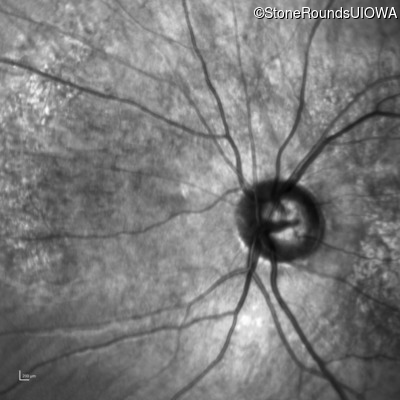

Infrared Fundus Photograph - Right - 10/200

Exemplar